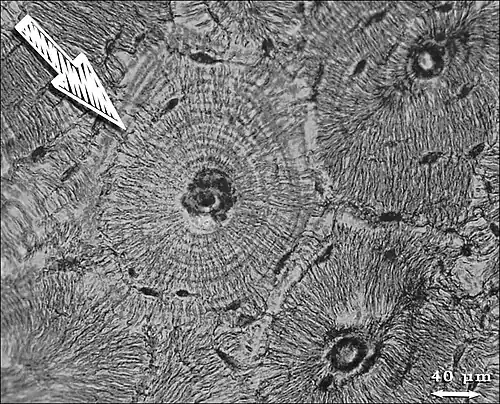

Osteon neboli Haversův systém je komplex koncentrických lamel a centrálního kanálu, které tvoří základní stavební jednotku kostí. Centrální kanál je označován jako Haversův kanál.[1]

Osteon má tvar dlouhého válce, je tvořen 4-20 koncentrickými lamelami. Vnější průměr mívá okolo 200 µm, jeho dlouhá osa leží rovnoběžně s dlouhou osou kosti.[1] Každý osteon je obklopen amorfním materiálem, cementovou substancí (mineralizovaná matrix s malým množstvím kolagenních vláken).[2] Haversův kanál uvnitř osteonu je na vnitřní ploše lemován endostem. Obsahuje krevní cévy, nervová vlákna a řídké kolagenní vazivo. Kanál komunikuje s periostem, s kostní dření i s ostatními Haversovými kanály příčnými nebo šikmými kanály Volkmannovými.[1] Volkmannovy kanálky nejsou koncentrickými lamelami obaleny, nýbrž jimi pronikají.[3] Přivádějí cévy a nervy z periostu k Haversovým kanálům.[1]

Kost není neměnná struktura.[1] Rozměry osteonů jsou různé a závisí na počtu lamel. Během růstu a dokonce i ve zralé kosti probíhá neustále destrukce a znovuvýstavba osteonů. Najdeme pak vedle sebe zralé osteony s mnoha lamelami a nezralé, tvořené pouze několika málo lamelami a širokým kanálkem.[4] Přestavba kosti je zahájena tím, že do kostní tkáně spolu s kapilární kličkou pronikají osteoklasty. Vytvářejí v kostní tkáni tunel s průměrem okolo 200 µm, který představuje prostor pro příští osteon.[1] Každý osteon vzniká postupným přikládáním lamel zevnitř, takže první lamela vzniká na periferii a kanál je široký. Přibýváním lamel dovnitř se kanálek postupně zužuje. U zralého osteonu tedy obklopuje Haversův kanálek naposledy vytvořená lamela.[4]